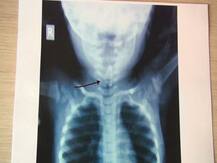

11 महिन्यांच्या चिमुकलीच्या अन्ननलिकेत सेफ्टी पिन अडकली!